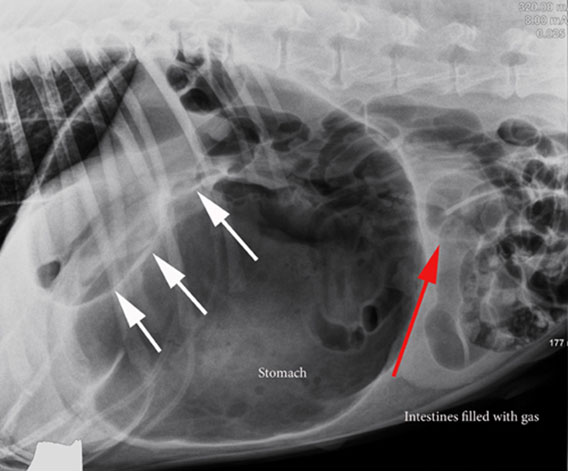

In caso di dilatazione gastrica, il gas o il cibo dilatano lo stomaco molto di più rispetto alle dimensioni normali, causando dolore addominale.

Per ragioni non completamente chiarite questo stomaco disteso ha tendenza a ruotare sul proprio asse strozzando l’apporto vascolare e chiudendo le vie di fuoriuscita al gas contenuto al suo interno. Questa condizione non solo é estremamente dolorosa ma mette anche a repentaglio la vita dell’animale in maniera molto veloce.